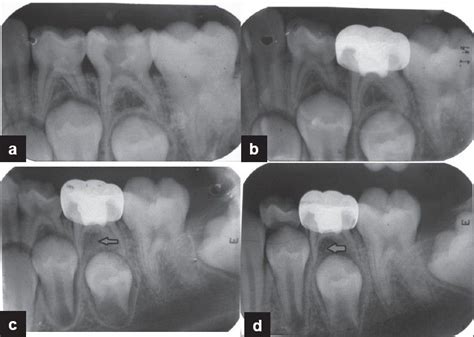

Radiographic features of the teeth treated with formocr ...

Radiographic features of the teeth treated with formocr ... from openi.nlm.nih.gov